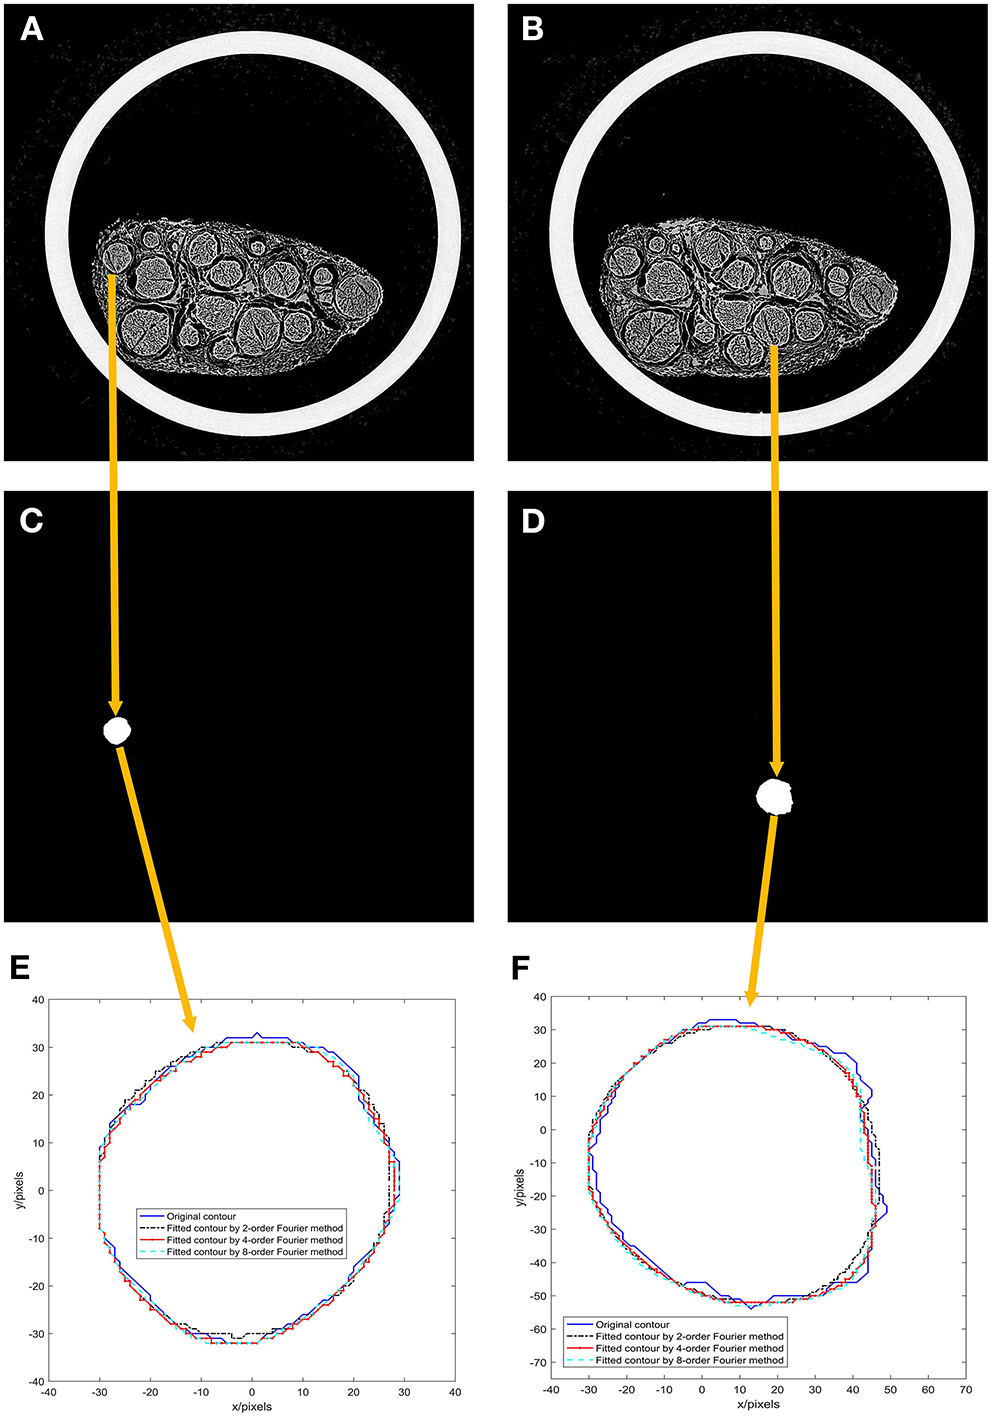

The first and 46th images among the 522 scanned sequence images of the specimen were chosen, as shown in Figures 5A,B.

Results of experiment 2. (A) 1st image of the 522 scanned sequence images of the specimen; (B) 46th image of the 522 scanned sequence images of the specimen; (C) A binarized image of the 1st scanned image; (D) a binarized image of the 46th scanned image; (E) Fourier models of the 1st scanned image; (F) Fourier models of the 46th scanned image.

A nerve bundle is chosen in Figures 5A,B, the algorithm is used to extract its contour, and a binarized image is obtained, as shown in Figures 5C,D.

The contours of the two nerve bundles were modeled using the 2nd-, 4th-, and 8th-order Fourier methods, and the results are shown in Figures 5E,F.

From the modeling results in Figures 5E,F, it can be seen that the curve fitted by the second-order Fourier model has a relatively significant difference from the original contour. Moreover, the curve fitted by the fourth-order Fourier model has a relatively small difference from the original contour. The curve fitted by the eighth-order Fourier model is very close to the original contour.